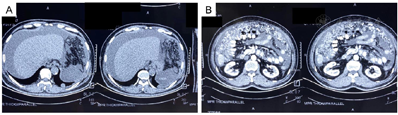

予3周期上述方案治疗后,患者腹胀、胸闷症状明显缓解,全腹增强CT示:腹水明显减少,腹膜、网膜、肠系膜及膀胱直肠陷凹弥漫腹膜增厚伴多发结节,较前明显减少。

行3周期上述治疗后,患者腹胀、胸闷症状明显缓解,全腹增强CT(图8):腰背部原术区未见肿瘤复发征象;腹膜、网膜、肠系膜及膀胱直肠陷凹弥漫性增厚伴多发结节,但较前明显减少,提示目前治疗方案有效。